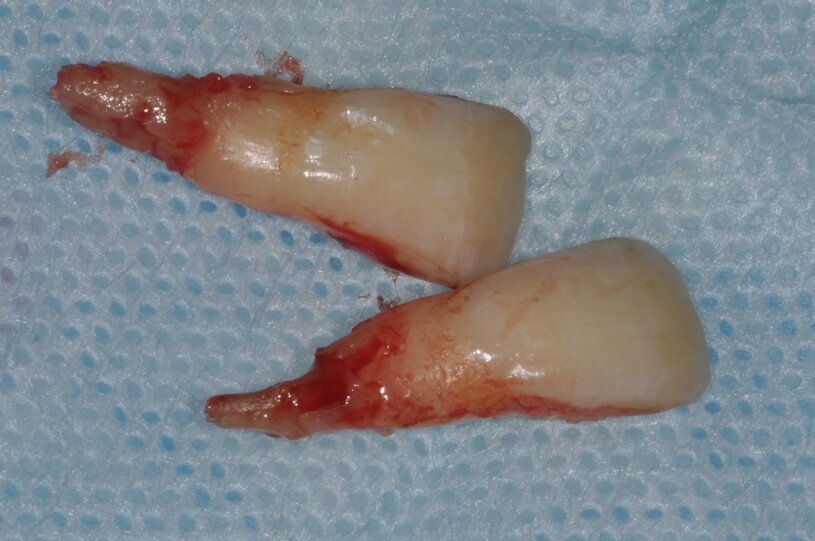

W dniu wizyty w poradni brak było oznak ostrego stanu zapalnego w okolicy 12-11. Widoczne były recesje dziąsła o wysokości 2 mm po stronie wargowej na zębach siecznych górnych przyśrodkowych, zmniejszona wysokość dziąsła zrogowaciałego do wartości 2 mm, spłycony przedsionek (Ryc. 1). Zęby były tkliwe na opukiwanie pionowe i poziome oraz wykazywały I stopień rozchwiania wg Entina. W przekrojach TK widoczny był rozległy przewlekły stan zapalny wokół wierzchołków korzeni zębów 11 i 21 (Ryc. 2), brak blaszki przedsionkowej wyrostka zębodołowego szczęki oraz resorpcja korzeni. Po wnikliwej analizie stanu miejscowego i rozmowie z rodzicami zadecydowano o ekstrakcji zębów 11 i 21 oraz w drugim etapie, ze względu na rozległy i zaawansowany proces zapalny, o autotransplantacji zawiązków 35 i 45.

Ryc. 3_Zęby 11 i 21 po ekstrakcji.